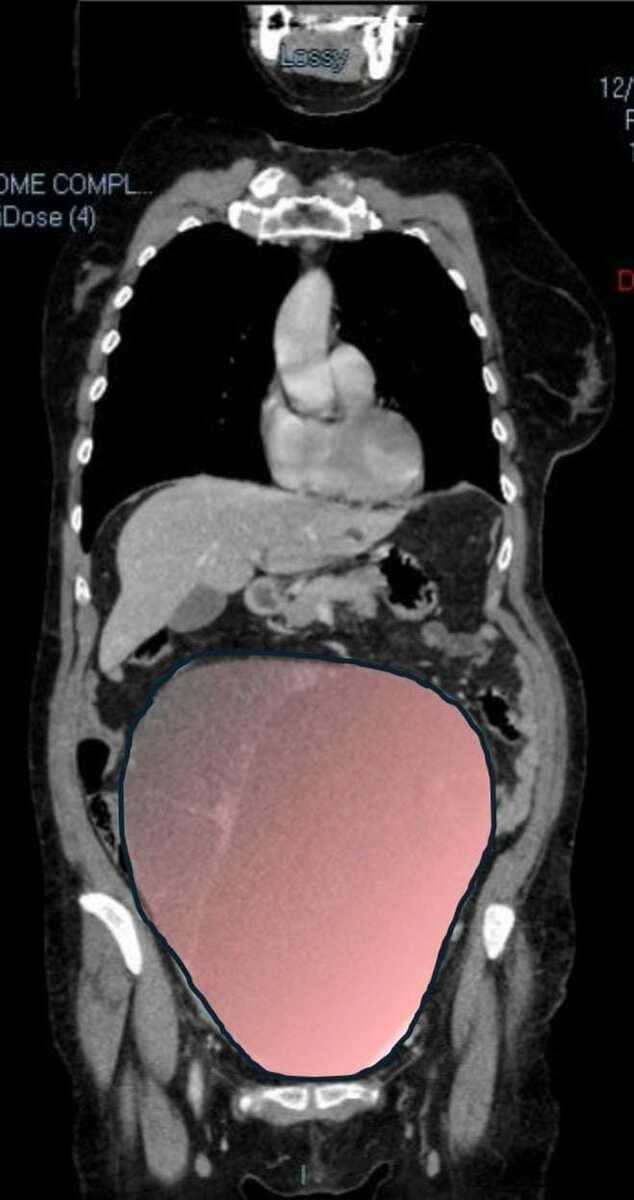

Per mesi la gigantesca cisti ovarica, con un diametro di circa 28 centimetri, è rimasta nascosta, senza dare segnali evidenti. La paziente non si era accorta di nulla. L’allarme è scattato quando la massa, associata alla presenza di una seconda neoplasia intestinale, ha iniziato a comprimere il colon, provocando sintomi acuti ed improvvisi fino ad una grave difficoltà intestinale non più ignorabile.

Durante l’intervento emerge tutta la gravità della situazione. La gigantesca neoplasia ovarica viene asportata: pesa circa 6 chilogrammi, con un volume paragonabile a quello di una gravidanza gemellare a termine. Ma non è l’unica minaccia. I sintomi più pericolosi sono legati alla sofferenza intestinale, che richiede un intervento immediato e coordinato di più specialisti.